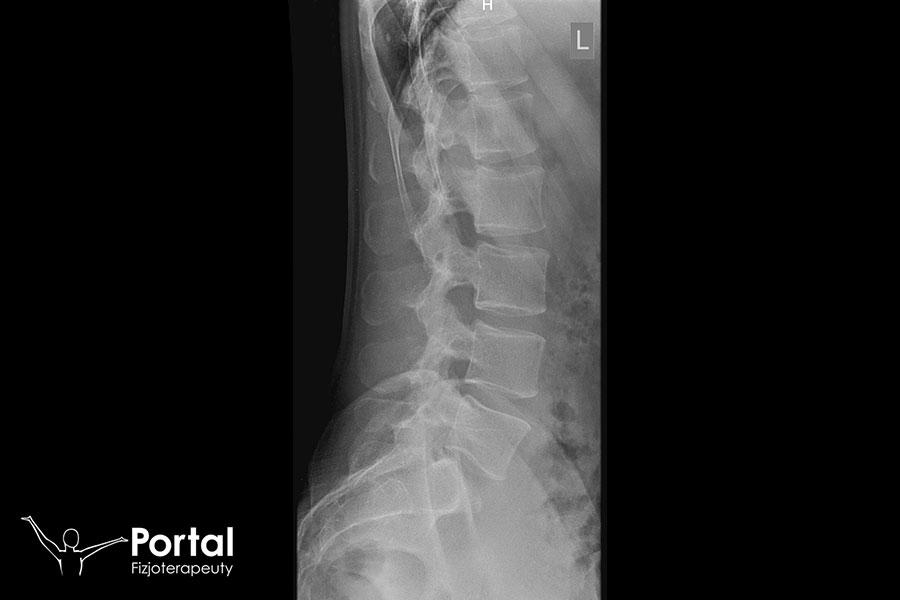

Przewlekłe bóle w kręgosłupie wymagają wykonania badań obrazowych, wśród których największe znaczenie ma rezonans magnetyczny. Ukazuje on zarówno kręgi i struktury kostne, jak i stawy, więzadła, kanał kręgowy czy krążki międzykręgowe. Z najwyższą precyzją pozwalają zdiagnozować m.in. dyskopatię, co nie jest możliwe na podstawie badania RTG. Jednocześnie warto udać się do fizjoterapeuty, który oceni napięcie mięśni i obecność na ich przebiegu tzw. punktów spustowych, które mogą generować ból kręgosłupa. Ważna jest też analiza postawy ciała i wykrycie ewentualnych wad postawy.